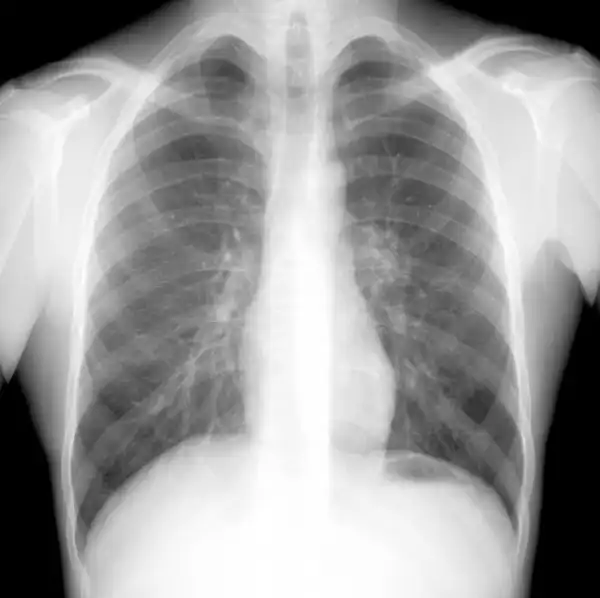

НОРМА: